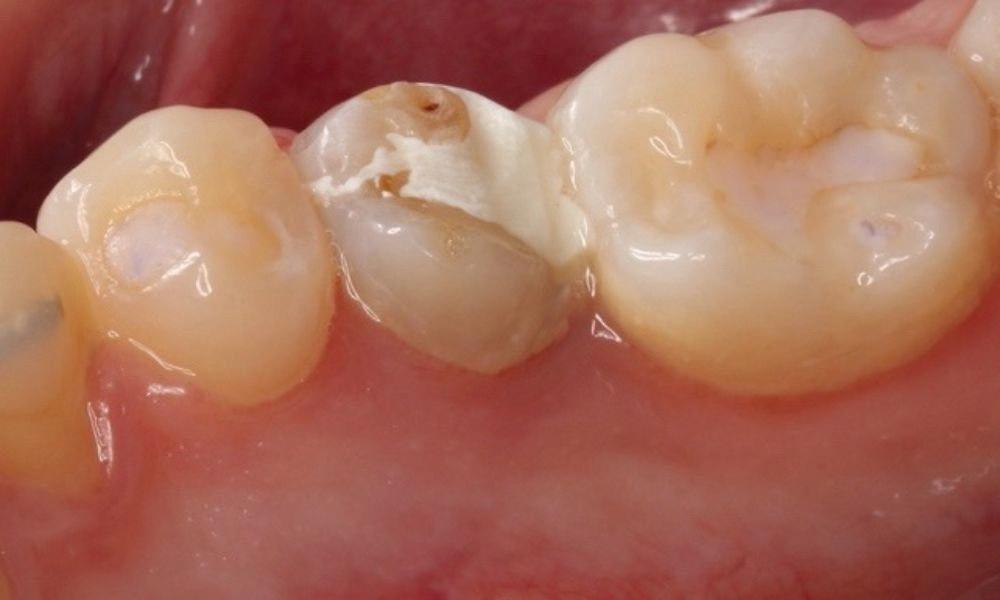

Estelite Asteria (Tokuyama)One of my favourite composite resin materials is Asteria which is a light-cured radiopaque composite for universal use. It considerably simplifies multilayer techniques yet delivers outstanding aesthetics with excellent polishability. Unlike mul tilayer techniques used with conventional composites, Asteria uses only 2 layers for optimal results without compromising aesthetics. The microstructure of the material produces a light diffusion that helps blend in with the natural tooth structure. The chameleon like nature of the material allows a blending of the materials to natural tooth structure and it allows excellent polishability which retains its lustre over time.